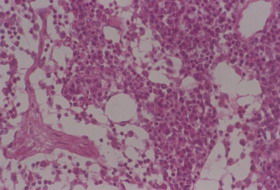

豬碘缺乏症 病豬表現為甲狀腺明顯腫大,生長發育緩慢,被毛生長不良,消瘦貧血。繁殖能力下降,母豬發生胎兒吸收、流產、死產或所產仔豬衰弱、無毛;部分新生仔豬水腫,皮膚增厚,頸部粗大,存活仔豬嗜睡,生長發育緩慢,死後剖檢可見甲狀腺異常腫大。臨診病理學檢查,血清蛋白結合碘、尿碘及甲狀腺碘含量普遍降低。

豬碘缺乏症 根據飼料缺碘的病史,臨診症狀見甲狀腺腫大、生長發育遲緩、繁殖性能減退、被毛生長不良可做出診斷。必要時進行實驗室檢查,測定飼料、飲水或食鹽的含碘量,測定血清蛋白結合碘含量,測定尿碘量等。